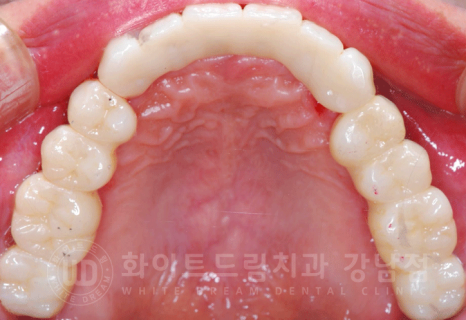

동일 인물이며 동일 환경에서 촬영되었습니다.

총 치료 기간 2017.06.03 - 2018.02.21 8개월 소요.

전악 임플란트는 낮아진 교합을 다시 설정하는 교합 거상술이 필요하기 때문에

보통 1년 정도의 기간을 두고 치료를 진행합니다.

치주염이 심해 거의 모든 잇몸뼈에 염증이 있는 상태였는데

3D CT를 통해 단단한 잇몸뼈 부위를 찾아 식립했으며, 1년 이내의 치료 기간이 소요되었습니다. ^^